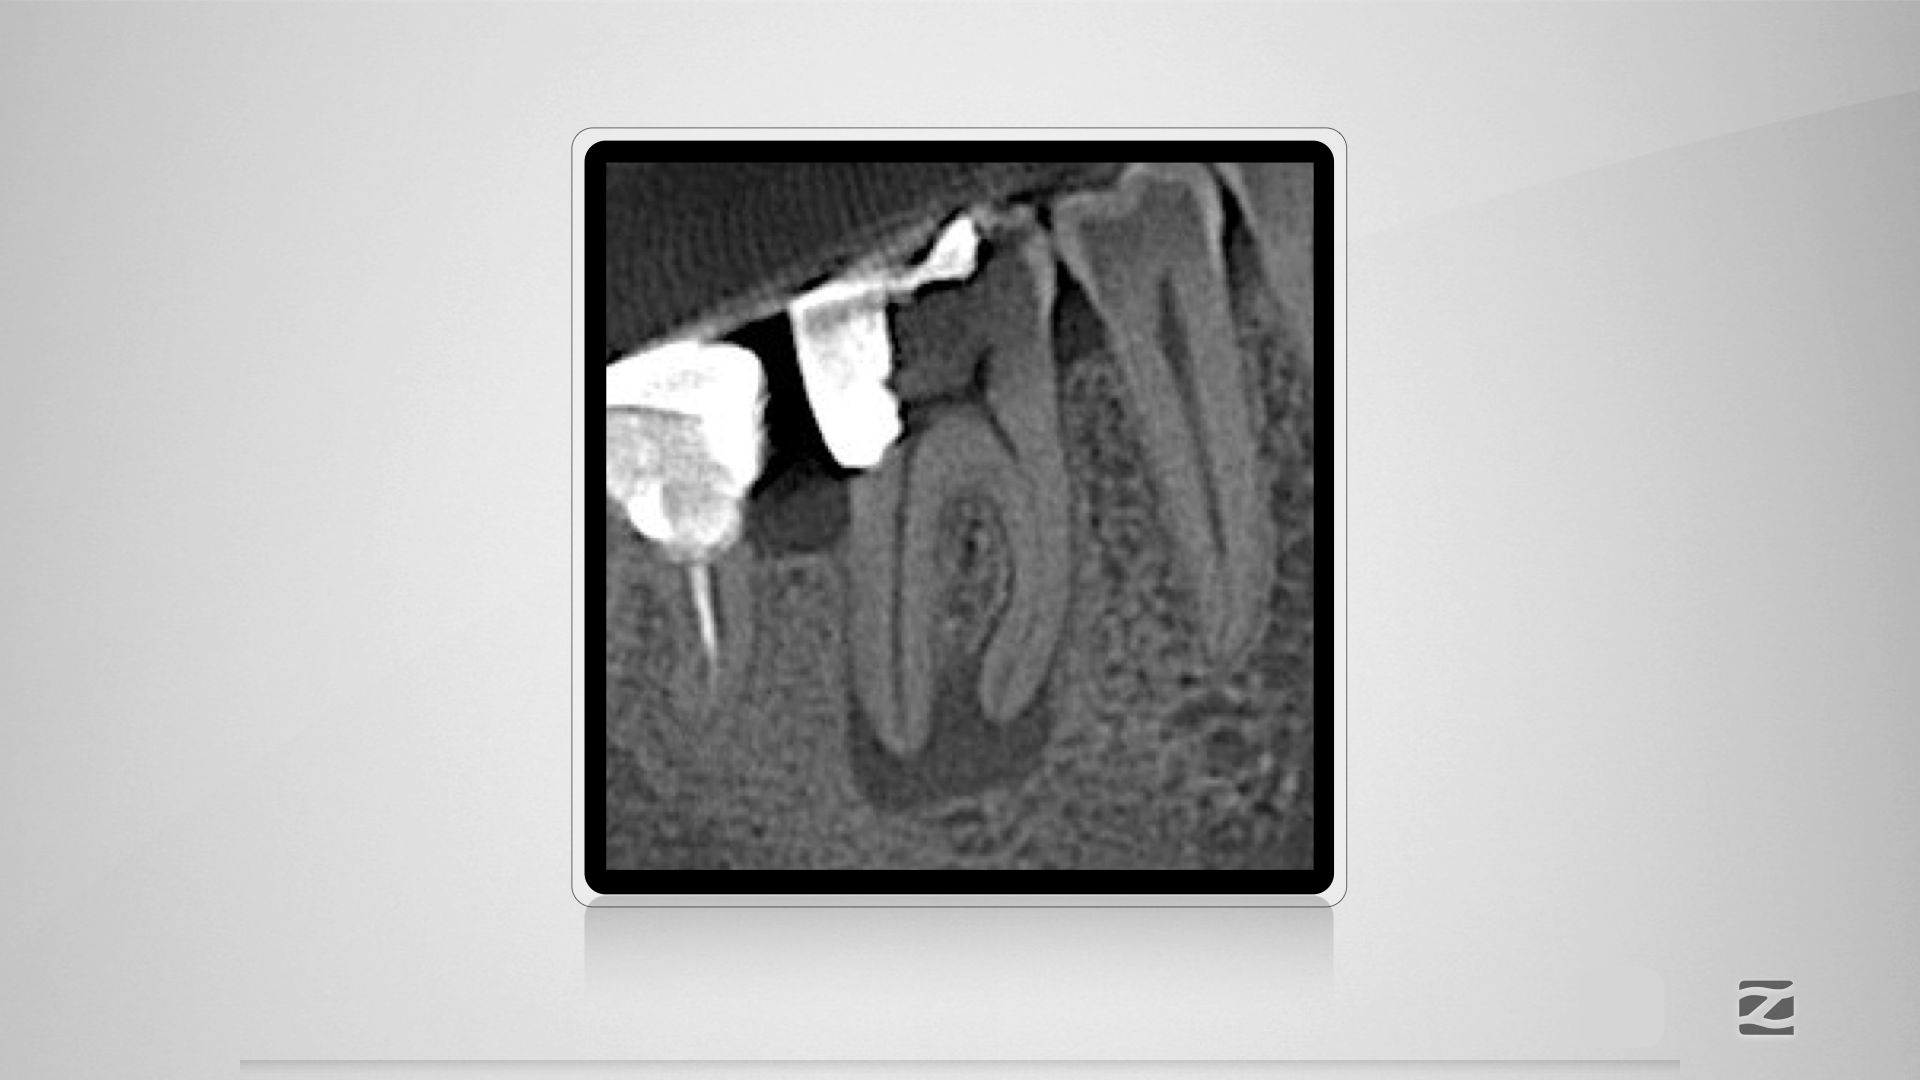

46D.002

Mit Navigation zum Erfolg